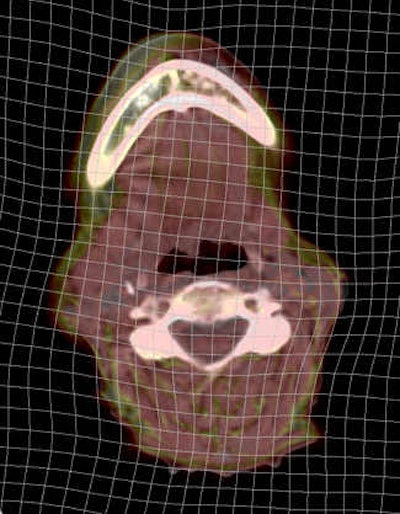

It is critical, however, that PET-MRI software provides tools for this purpose, including semitransparent overlays, checkerboard and inset views, and additional tools to assess the quality of the deformation itself. The resulting deformation should be free of tears and discontinuities. Representations of deformation are also important for assessing the alignment in areas of homogeneous tissue such as the liver in CT. Good-quality DIR should produce smooth motion in such areas and not create arbitrary deformations. Figure 3 shows one such display: the so-called deformation grid overlay. In the absence of deformation, the grid lines would be straight.

Figure 3: Examination of the deformation grid can facilitate quality assessment by the user. The deformation should be smooth, free from discontinuities, and not contain artificial deformation in areas of homogeneous tissue.There have been a number of studies done to validate the accuracy of DIR in the context of software PET-MRI. Work led by Dr. Martin Lodge and colleagues at Johns Hopkins University in Baltimore, Maryland, U.S., and presented in June at the 2013 Society of Nuclear Medicine and Molecular Imaging (SNMMI) meeting in Vancouver, British Columbia, looked at PET-MRI software registration in the context of prostate cancer (Journal of Nuclear Medicine, 2013, Vol. 54:supplement 2, p. 2089). A quantitative assessment of accuracy was performed using a catheter as a known point to measure target registration error. DIR significantly improved registration accuracy compared with rigid registration.